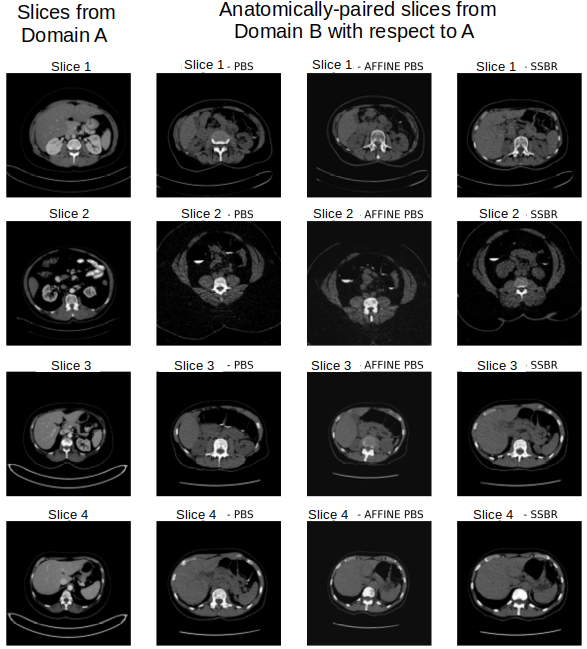

Despite the good results shown in the method identified as the best ones in Figure 5, in terms of overall shape and contrast intensity, the PBS selection was not sufficient and several anatomical artefacts appeared (see Figure 3). Another existing strategy for anatomically-paired selection that we tested was the use of 3D affine registration with Simple-Elastix [Marstal et al.(2016)Marstal, Berendsen, Staring, et al.] algorithm. Given the high variability between the two domains, we decided to perform the registration at each iteration between the two selected patients. Anatomical coherence was improved but some important artefacts still appeared. Finally, our proposed selection with SSBR was tested, which reduced the severity of artefacts, as shown in the forth column of Figure 3.

We then added the loss function, which significantly improved anatomical coherence, particularly in the binary mask regions. Eventually, we combined in a first moment the use of input as template and in a second moment the binary mask . The complete proposed method based on SSBR selection with , and produced high quality synthetic images, without visual artefacts and with realistic contrast intensity according to physicians’ evaluation. Some qualitative results are detailed in Figure 3.